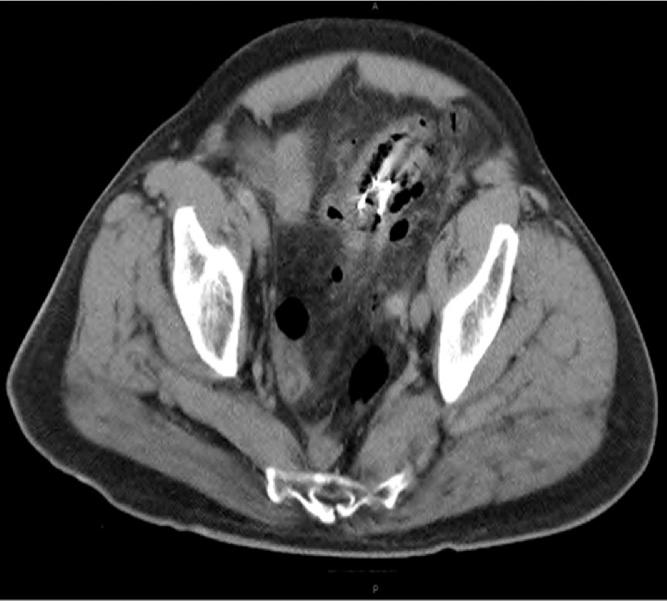

Rare case of an elderly male presenting to the emergency department with an acute abdomen few days post accidental ingestion of his dentures. A detailed history along with a CT abdomen showed perforation in the sigmoid colon adjacent to the site of the swallowed denture.

一名老年男性在意外吞食假牙几天后因急腹症就诊于急诊科,这种情况较为罕见。详细病史及腹部CT显示,乙状结肠在吞食假牙部位附近出现穿孔。